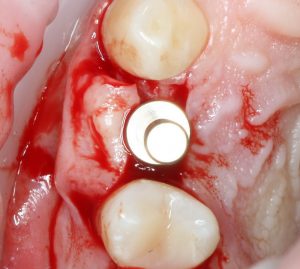

Еще раз проверим положение имплантата:

Учитывая то, что на нём уже установлен временный абатмент TempBase, сделать это очень просто. Фактически, сейчас мы с Вами видим картинку, которую увидит ортопед перед установкой коронки. Это очень удобно.

Больше нам абатмент TempBase не нужен, мы его убираем:

Без абатмента можно оценить позиционирование имплантата по глубине погружения. Напомню, что XiVE — это субгингивальная имплантационная система, поэтому ортопедическая платформа имплантата должна находиться на уровне костной ткани. Что и было выполнено в нашем случае.

И, коль всё в порядке, переходим к следующему этапу операции — установке формирователя десны.